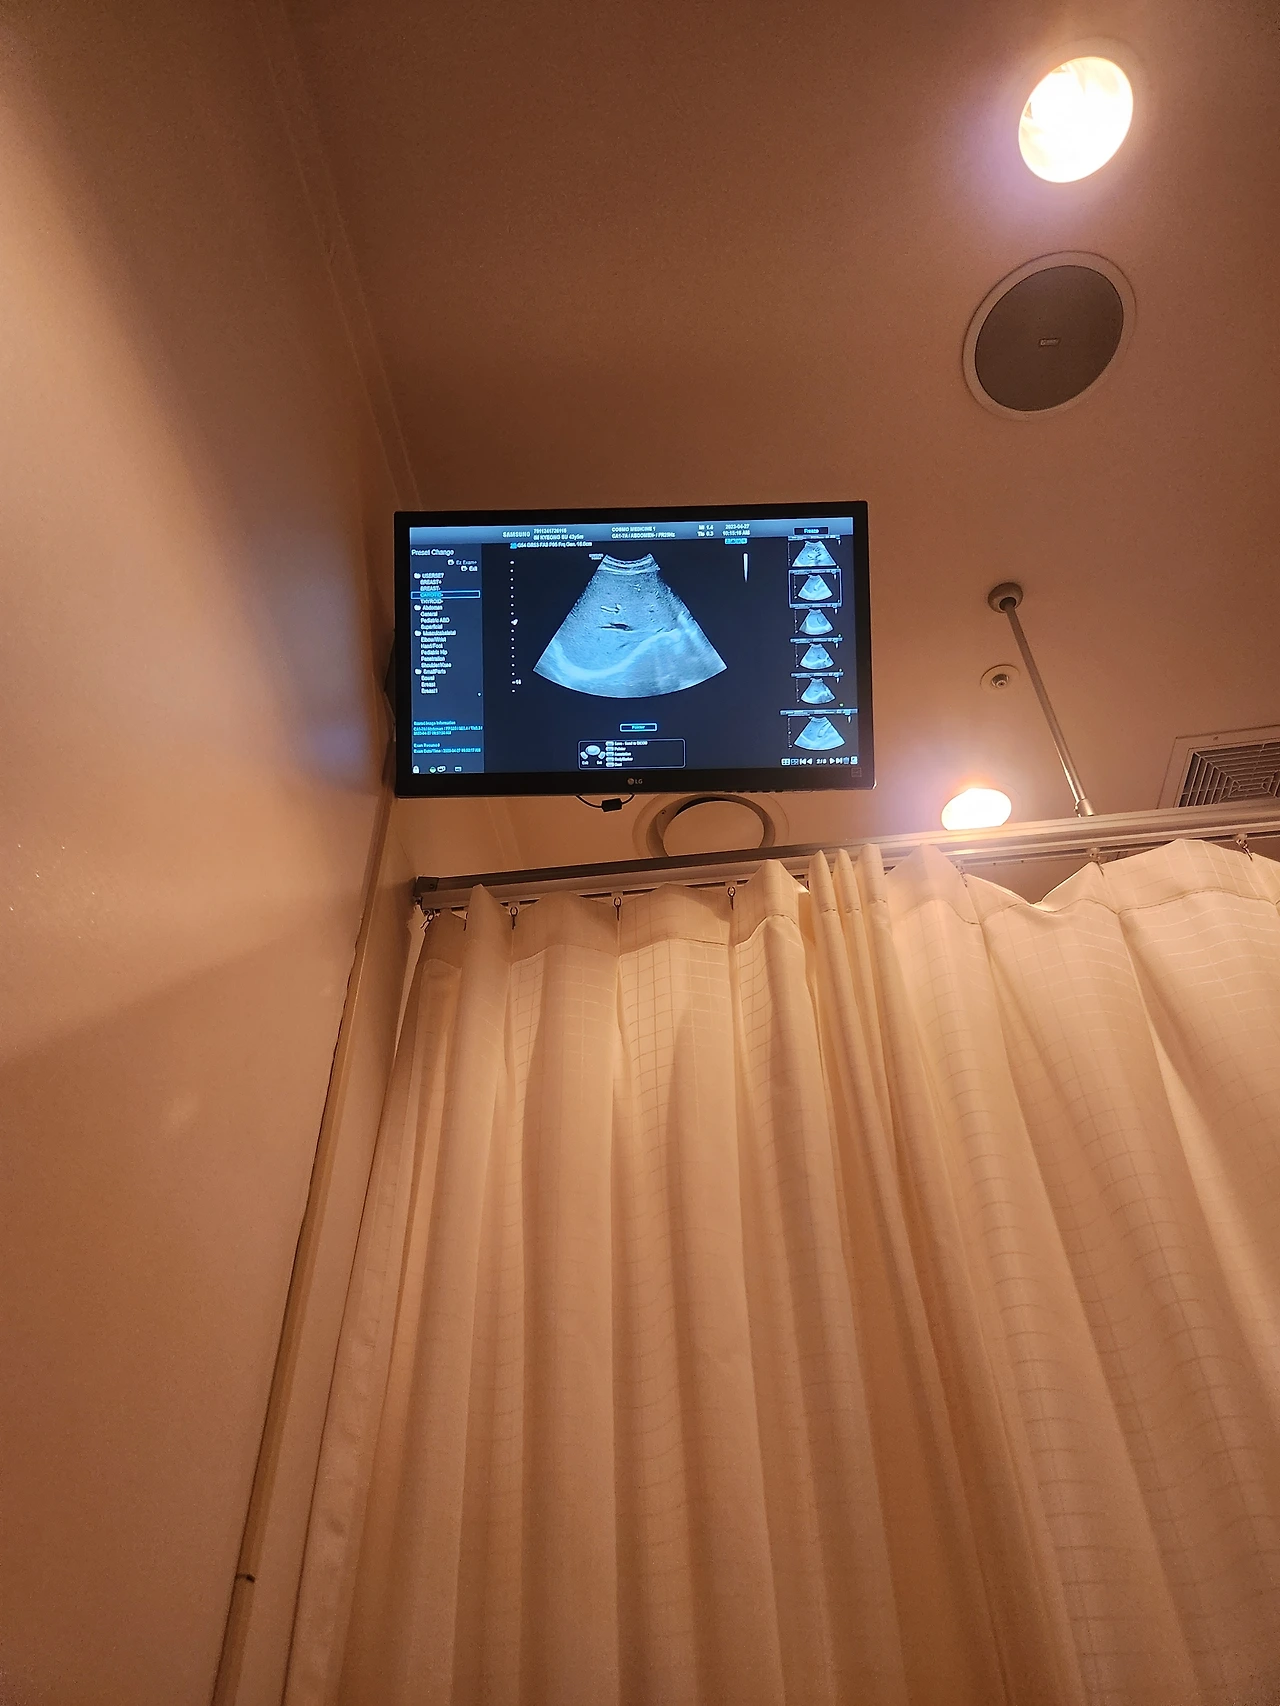

유방암 6년 검진 3일차

메인 유방갑상선 초음파

초음파 침대에 눕는 순간,

우리의 심문 같은 대화는 어느새 수다로 변하고 초음파 딸깍 소리에 숨이막히는 나의 심장을 선생님께서 진정시켜주고 있었다

특별히 이상은 없네요.

그렇게 나의 메인 본게임 검사는 끝이났고